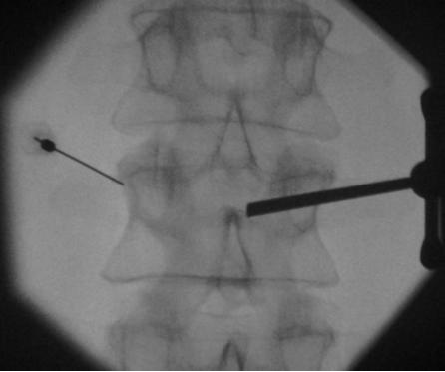

骨肌肉活检的引导

Guidance CT 轴向精度 透视:Caudo-cranial 精度

有骨遮挡的病变:病变的深度(Depth)和病变的硬度(consistency)-成骨性病变或溶骨性病变

椎体成形术的穿刺针